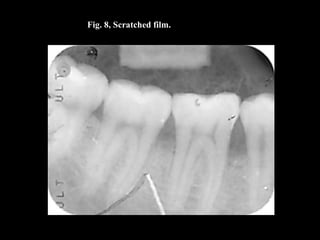

Fig. 8, Scratched film.